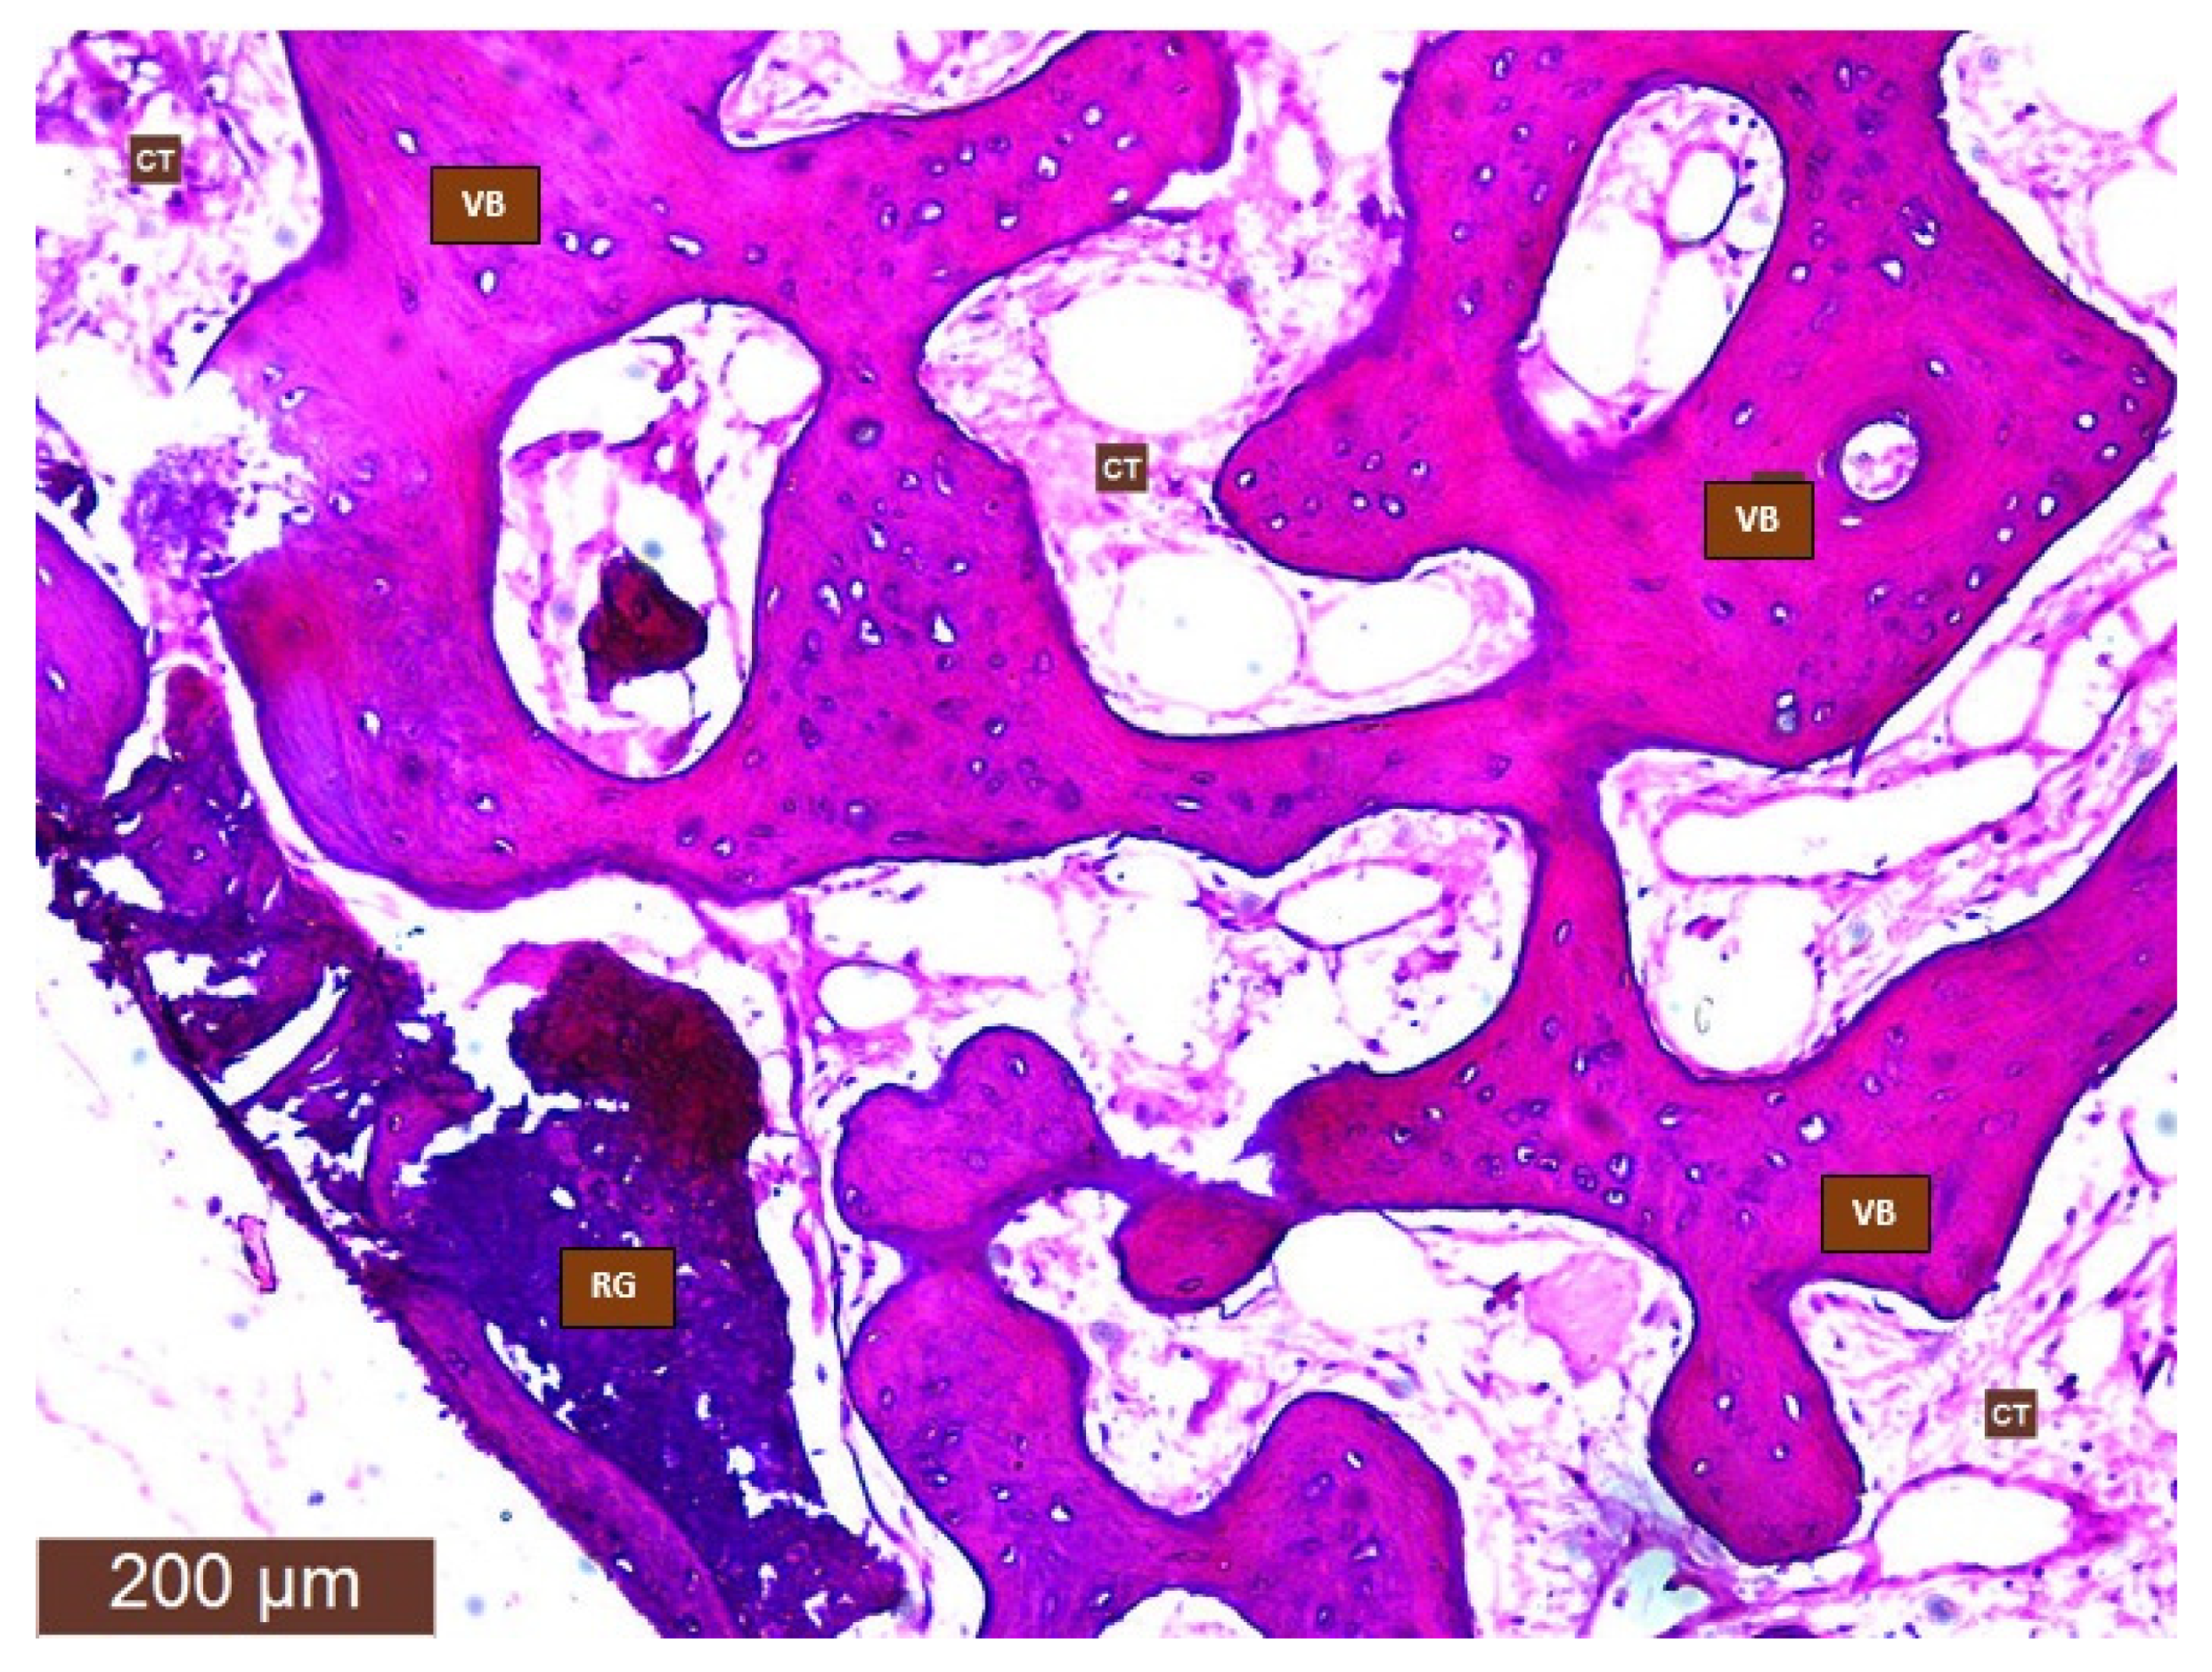

The bone samples were removed from the trephine burr and stored in a small jar with a 10% formalin solution for 12–24 h. The bone fragments were decalcified (decalcifying solution: EDTA; microwave oven: 8 cycles of 10 s at 41–43 °C for 20 min, after each cycle of the microwave oven the decalcifying solution was changed). In the next step (paraffin incorporation), the material was dehydrated with an alcohol series: 70% ethyl alcohol, 95% ethyl alcohol, 99% ethyl alcohol and clarified with xylene. The bone fragments were embedded in a paraffin block, cut into slices (3–4 microns), and stained with Hematoxylin–Eosin (Figure 4).

Digital pictures of the microscopic samples were taken and imported into a free image processing program (Fiji/ImageJ) [18]. In the software the percentages of newly formed bone, connective tissue, residual bone graft, and immature bone were calculated (Figure 5a–c). The latter were measured in pixels and converted to percentages. Measurements were performed by two independent researchers.

Figure 4. Histological preparation of post-extraction socket four months after tooth extraction. (VB: vital bone; CT: connective tissue; RG: residual graft).